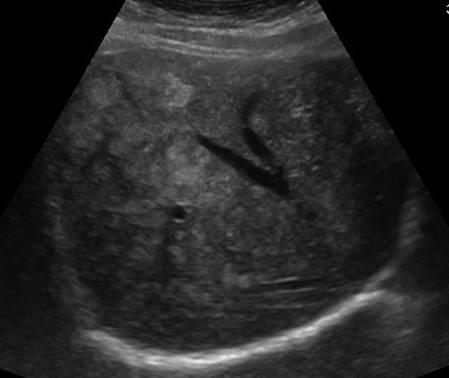

Gan nhiễm mỡ

Gan nhiễm mỡ - Ảnh 4

» Thông tin: Nữ giới – 40 tuổi.

» Lâm sàng: Kiểm tra sức khỏe.